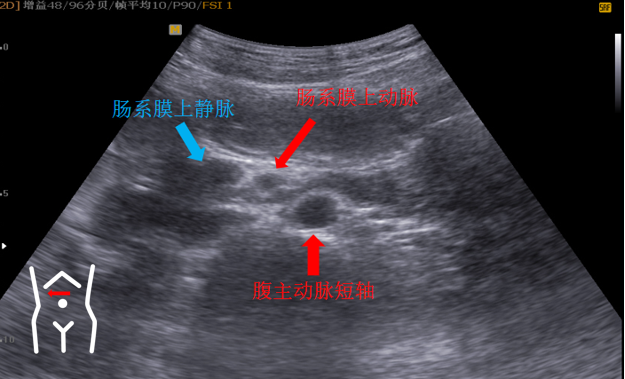

第五组切面

十二指肠水平段穿越肠系膜上动脉上静脉与腹主动脉间隙切面。